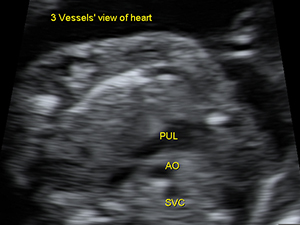

胎兒心臟三血管平面圖